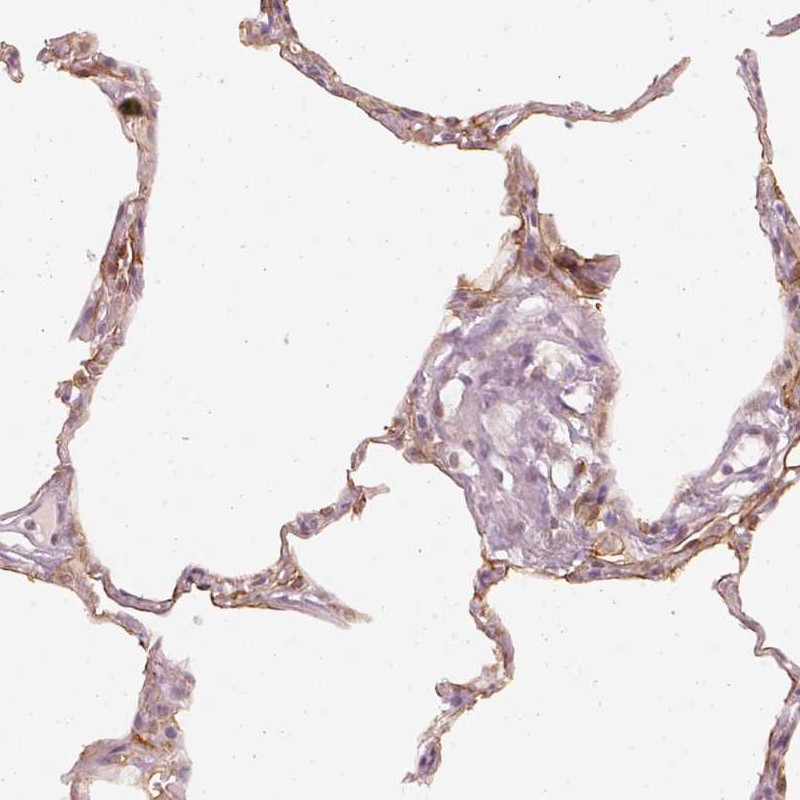

Immunohistochemical staining of human lung shows moderate membranous positivity in pneumocytes.